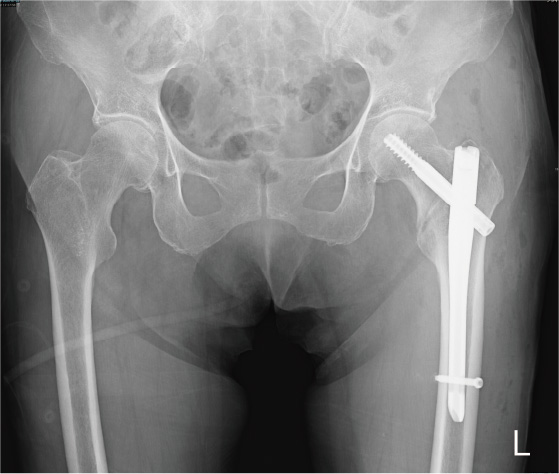

大腿骨頚部骨折は股関節内に骨折線があるため治りにくい骨折です。ほとんどずれていない(非転位型)大腿骨頚部骨折に対してはスクリューなどを用いた骨接合術を施行します(図1)。手術侵襲が少なく、術後感染や輸血の可能性も低く、歩行能力を回復しやすい骨折だと思います。

大腿骨転子部骨折は股関節の外に骨折線があるため骨癒合しやすい骨折であり、髄内釘による骨接合術を施行します(図3)。ただし、輸血が必要となる可能性が高く、術後痛みが強い傾向にあるため、歩行能力の獲得には時間を 要すると思われます。